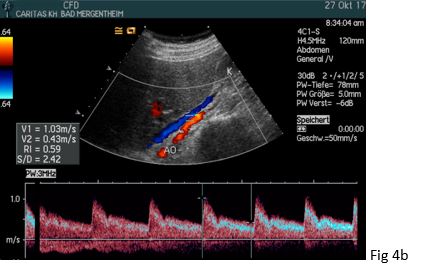

Figure 2: The retrocavally located right renal artery could be visualized posterior to the inferior vena cava (IVC) with a bruit in (a) and turbulent flow above 4 m/s in (b).

Figure 4:(a) A normal and low-resistance Doppler spectrum was demonstrated one day after dilatation of the right renal artery (in between markers) without a bruit and turbulence.

(b) There was a PSV/EDV of 103/43 cm/s (RI = 0.59) (AO: aorta). .